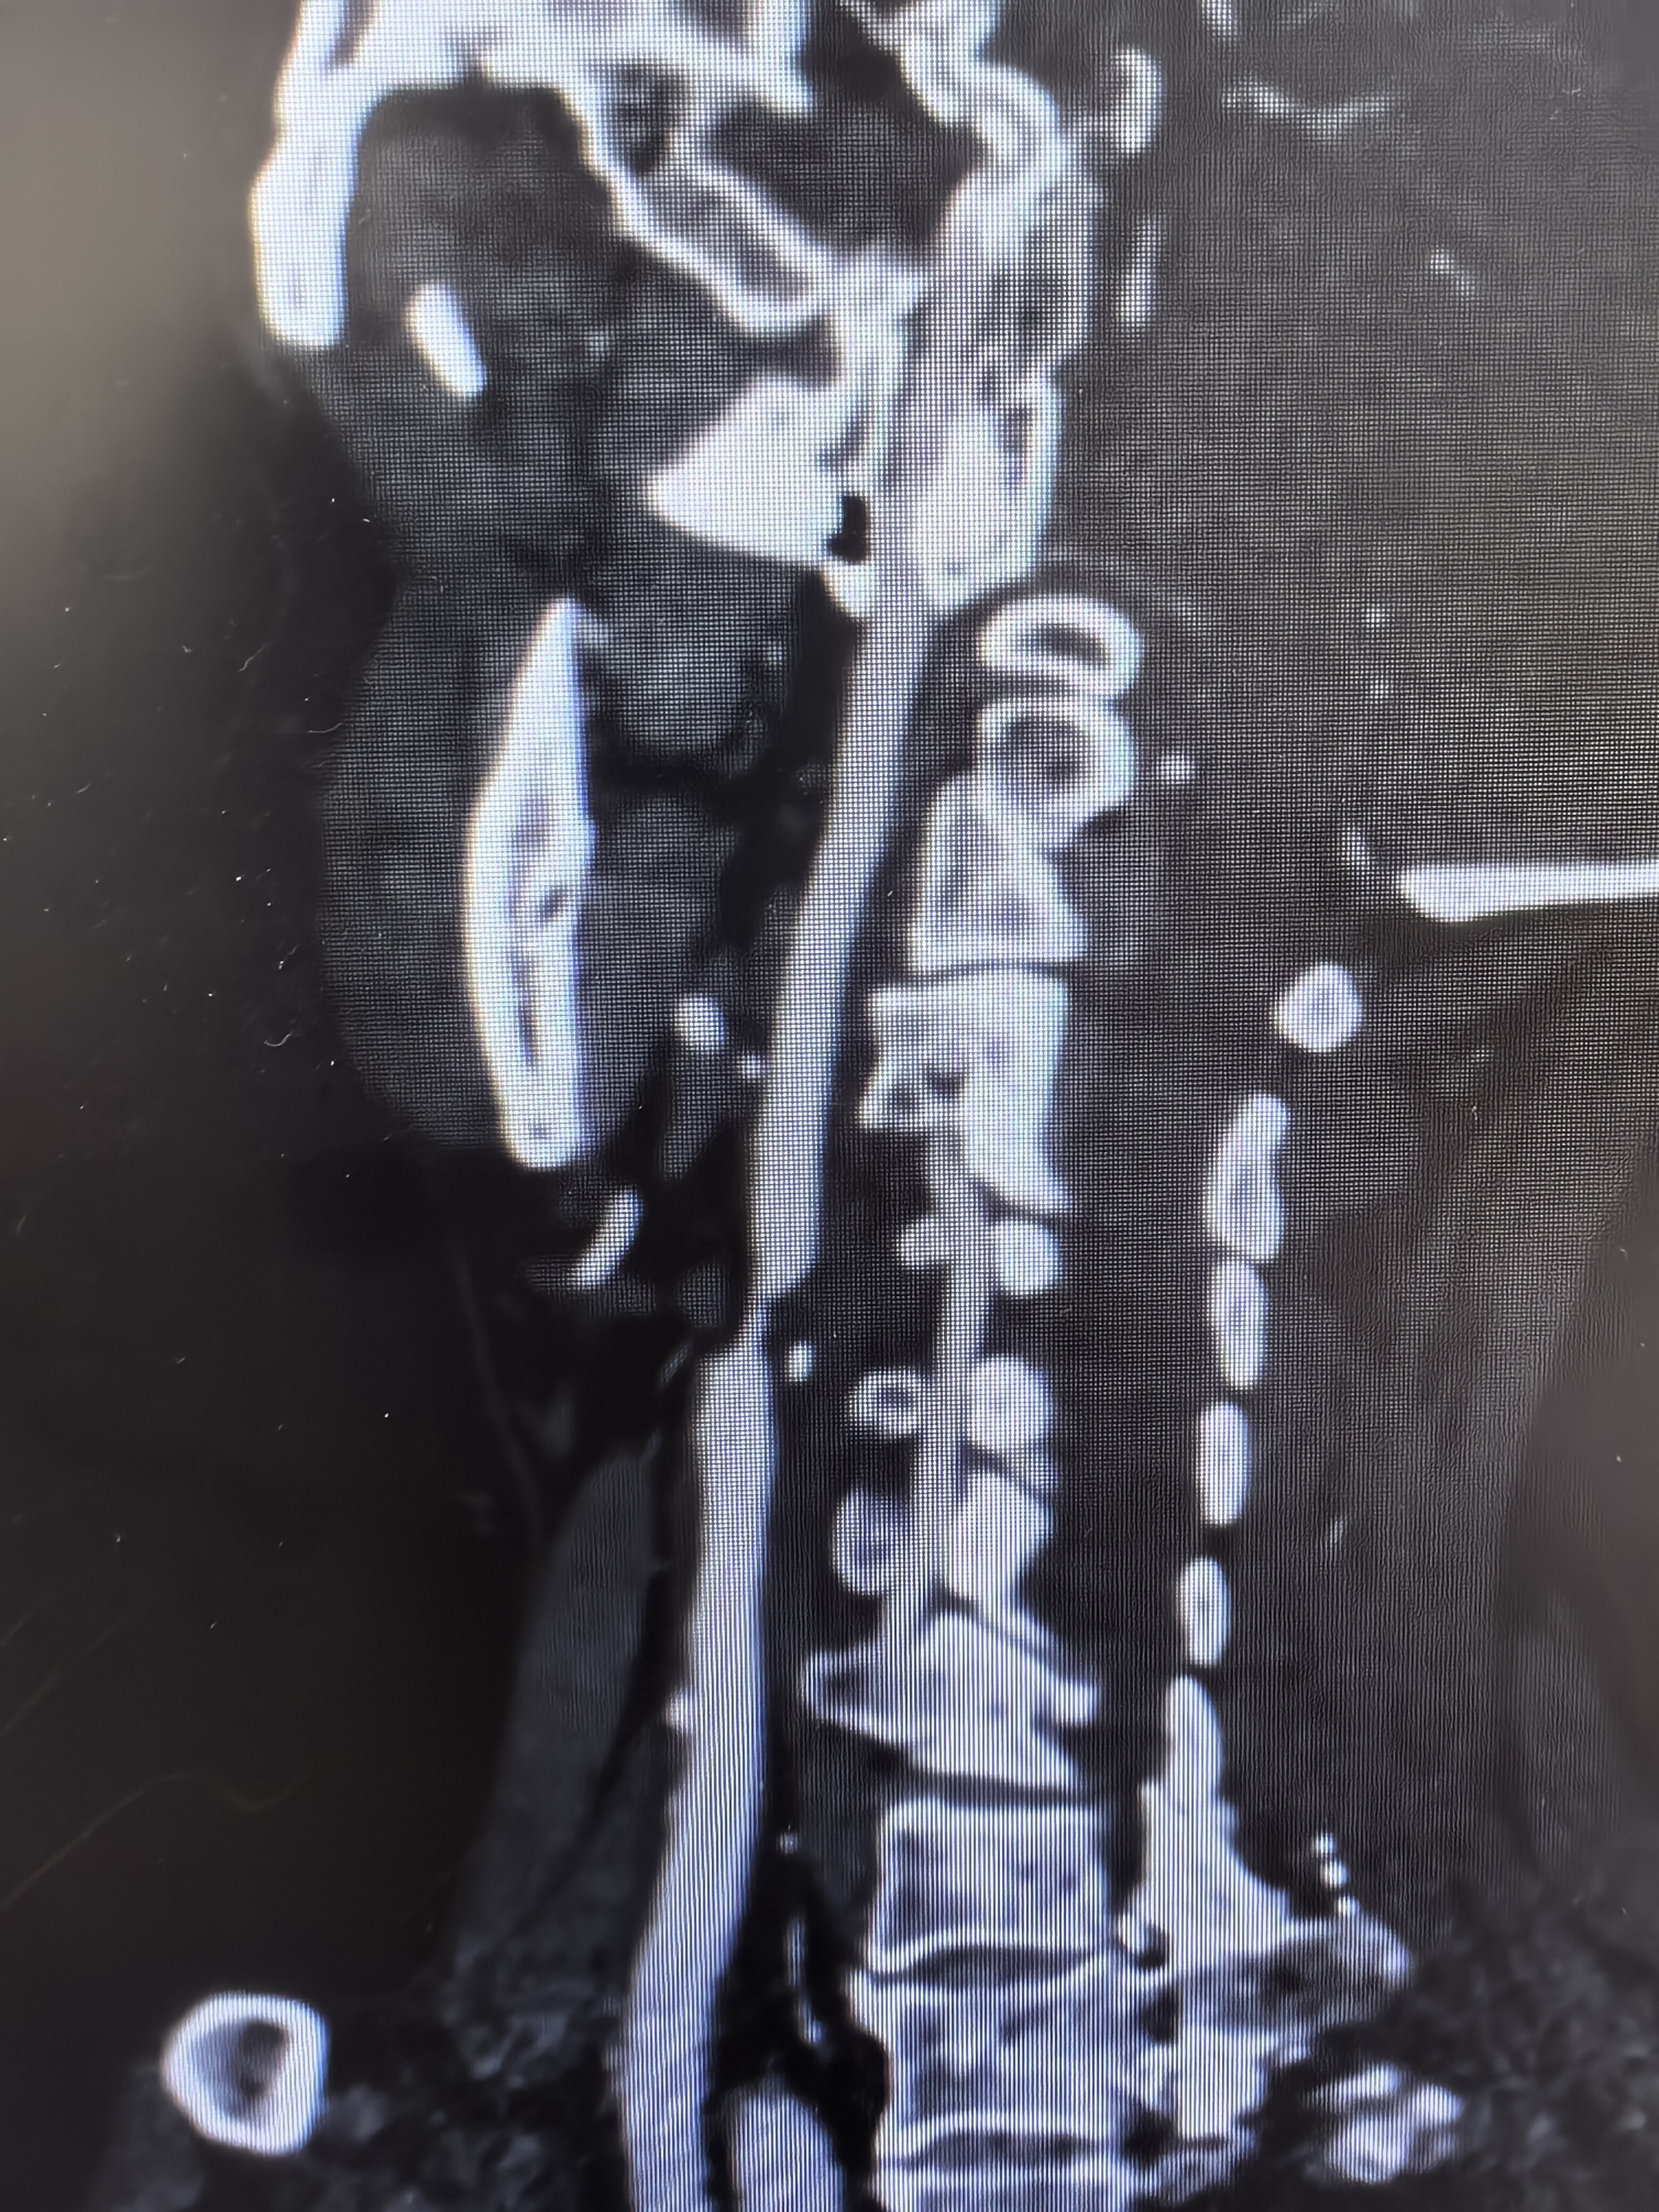

治療前患者男性,41歲,既往高血壓、高脂血癥病史,有吸煙及飲酒史?;颊?月前出現(xiàn)枕葉和小腦梗塞,1月前在當?shù)匦蠨SA發(fā)現(xiàn)左側椎動脈V1-V2(至C5水平)閉塞,枕動脈肌支自V3供血,并向近心端返流至C5水平,呈震蕩血流,考慮梗塞是由于震蕩血流造成椎動脈內斑塊脫落引起,患者存在罕見的椎動脈殘腔綜合征(VertebralArteryStumpSyndrome,VASS),這是后循環(huán)缺血性卒中的少見原因。治療中治療方案:因椎動脈起始端閉塞過長,故設計手術方案為頸外動脈-橈動脈-椎動脈搭橋(ECA-RA-VAbypass),術中行腦氧、TCD和電生理監(jiān)護等多模態(tài)監(jiān)護。該患者情況因為既往放置主動脈內覆膜支架無法行介入微創(chuàng)治療。治療后治療后1年術后腦灌注CT對比術前改善,術后患者訴視物光線較術前明亮清晰,術后一年復查搭橋血管通暢良好。